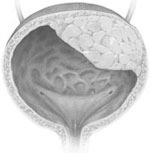

Мочевой пузырь – рак

Эта патология распространена у курильщиков — мужчин старше 40 лет.

Гематурия – кровь в моче — это первый и, зачастую единственный симптом заболевания.

На более поздних стадиях могут присоединиться боль в области таза и промежности, затруднение и болезненность при мочеиспускании.